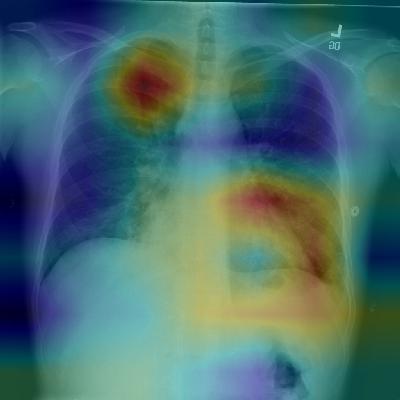

(a) Patient with multifocal community acquired pneumonia. The model correctly detects the airspace disease in the left lower and right upper lobes to arrive at the pneumonia diagnosis.

(b) Patient with a left lung nodule. The model identifies the left lower lobe lung nodule and correctly classifies the pathology.